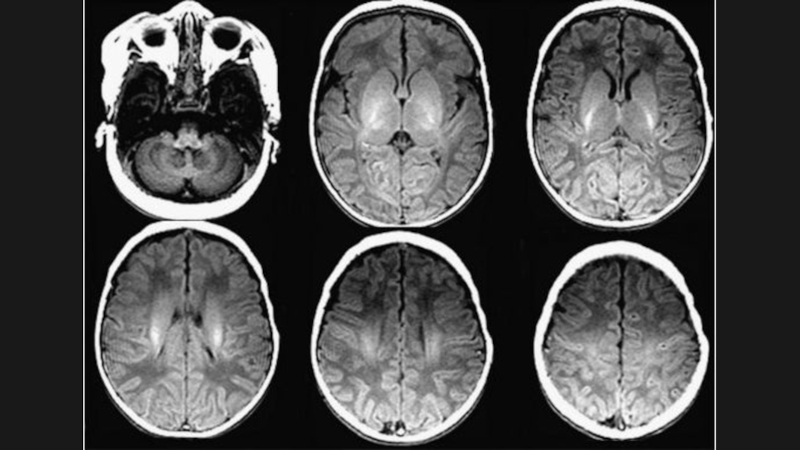

Слайд 173 мес.

8 мес.

3 мес.8 мес.